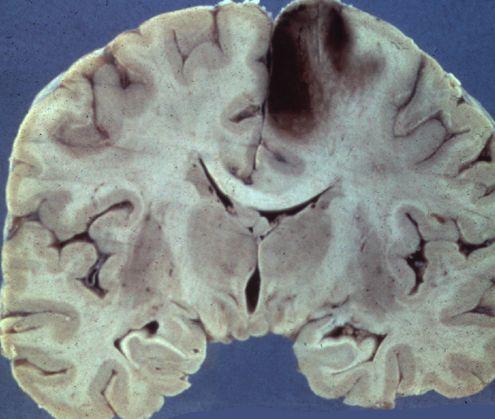

Cum arată CREIERUL UMAN după un ATAC CEREBRAL

Foto: neuropathology-web.org